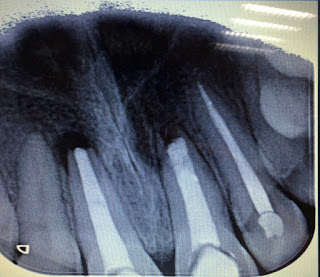

Se trata de una paciente de 45 años con dolor en el 3º cuadrante. Se le hace rx de diagnóstico y tiene una caries distal distal invadiendo parte de la raiz distal.

La dificultad de este molar que Diana solventa muy bien es la caries distal que invade parte de la raíz y a la paciente se le explica el tto. y las opciones y se le advierte de las posibles complicaciones debido a la proximidad de la caries al espacio periodontal.

Se sella la cavidad de la caries con MTA una vez sellados los conductos y evitar asi la filtración posterior a través de la caries.

Las longitudes de los conductos fueron: mv: 24mm , ml: 23,5mm d: 24mm.